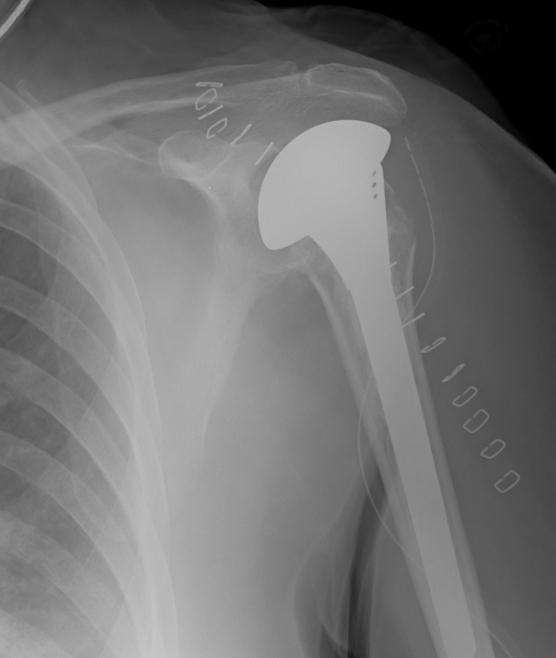

proximal humerus fracture Background ORIF with locking plate Arthroplasty Greater tuberosity fractures Lesser tuberosity fractures / avulsions Book traversal links for Proximal humerus fractures ‹ Pectoralis Major Tears Up Background ›